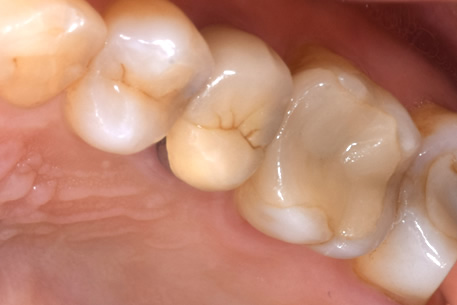

写真で見るとわかるかもしれませんが、初期の虫歯は着色して茶色くなっています。

この場合、茶色い部分を探針で探ってみると硬い場合がほとんどで虫歯の柔らかさを感じることがありません。

初期虫歯は、ほとんどの場合が石灰化して白くなった部分に着色している状態が多いですね。

そのため、患者さんから見えるような部分ですと多くの患者さんがこれは虫歯なのではないか?と聞かれることがあり、レントゲンを撮ってみると虫歯のような影もなく、探針で触ってみても硬い場合がほとんどです。

初期虫歯の状態の抜歯後の歯の写真